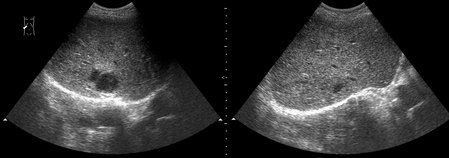

Маленький абсцесс печени до и на фоне 1 недели АБ-терапии

abscess-one_week_treatment.jpg

А какие ограничения для дренирования были в данном случае?

Плохая доступность. Был расположен очень высоко и был небольших размеров.

Решено было вести консервативно.